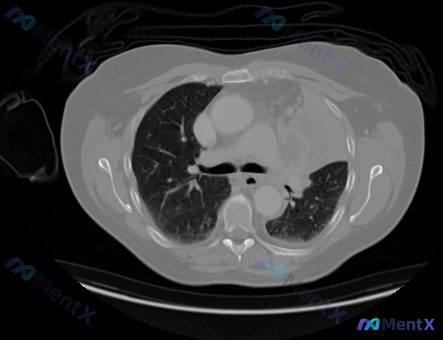

整理了一份挺有警示意义的胸部CT病例,影像和临床思路结合起来看很有启发。 --- 先看影像核心发现 胸部CT(纵隔窗)横断面: 1. 纵隔占位:前纵隔及中纵隔左侧可见一巨大软组织密度肿块,呈分叶状,密度基本均匀;占据纵隔空间,对周围结构推压明显——气管向右侧移位、管腔受压变窄;上腔静脉及周围大血管向...